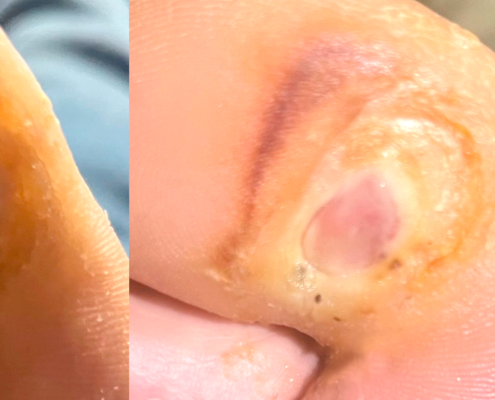

A continuación, te invitamos a explorar una selección de casos clínicos de terapia diamagnética que destacan por sus resultados sobresalientes. Haz clic en cada caso para conocer los detalles del diagnóstico, el tratamiento y los resultados obtenidos.

La terapia diamagnética ha revolucionado la manera en que tratamos diversas afecciones, desde lesiones deportivas hasta dolencias crónicas. En esta página, encontrarás una recopilación detallada de casos clínicos de terapia diamagnética, mostrando cómo este tratamiento innovador ha ayudado a nuestros pacientes a mejorar su calidad de vida.